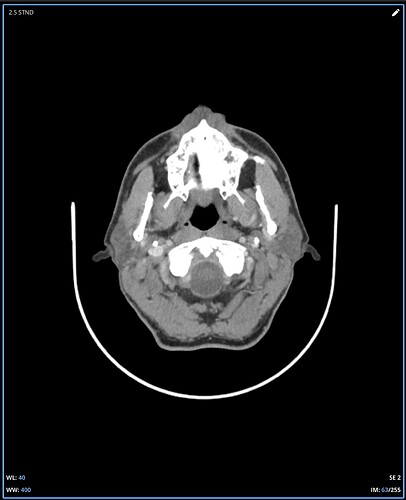

I’m not good at tech so can’t do labels or arrows for your imaging, but on the first two images, there’s clear compression of the IJV between the styloid process & the C1 process. In the first one, it’s not clear whether it’s just the imaging or whether there’s also narrowing of the IJV further down- it disappears so that could be compression but can’t see clearly, if it was compressed there it would indicate TOS which might explain some of your arm symptoms…

In the other two CT images, you can see the styloids really clearly- they’re quite elongated, pretty thick right at the top, and both sides look close to the C1 processes, which is a common place for the IJVs to get compressed.

Where I am in Canada and the healthcare system is slow, I travelled to a different province in November for an updated CT. The report did note a pretty severely squished left jugular between C1 and the styloid and some compression on the right side as well so at least it is acknowledged on a report now. It sure looks like C1 is causing a problem even moreso than the styloid but I am not in a position to figure this out. I can’t help but wonder if I was born this way and it’s actually not the problem at all. Anyway, I would appreciate any feedback whatsoever on these new images….is a C1 shave a must do? I hope this isn’t too many images to post, I was trying to show the full picture of how the compression looks. It is very difficult to pick out the left jugular because it becomes so small:

It’s clear that your right IJV is dominant based on its size vs the left one. I’ve annotated a couple of your 3D images to show what I see & will comment below them. Scrolling through your axial images, it’s obvious you have significant bilateral IJV compression.

Your left IJV appears to be predominantly compressed by C1 as you suggested, however, there is secondary compression lower down which appears to be caused by your ICA, however, it could be coming from your SCM which could be impacting both the left IJV & ICA.

Your right IJV appears to have a small clot at the level of the C1 compression, although this could simply be C1 pressing from the back side. I’d sure talk to a doctor about the way that looks though.